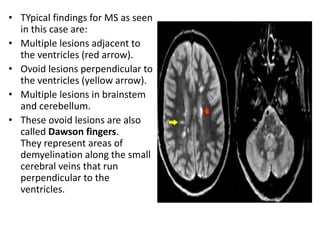

• TYpical findings for MS as seen

in this case are:

• Multiple lesions adjacent to

the ventricles (red arrow).

• Ovoid lesions perpendicular to

the ventricles (yellow arrow).

• Multiple lesions in brainstem

and cerebellum.

• These ovoid lesions are also

called Dawson fingers.

They represent areas of

demyelination along the small

cerebral veins that run

perpendicular to the

ventricles.

DAWSON FINGERS

the ventricles (Dawson fingers).

• Enhancing lesion.

• Multiple lesions adjacent to the

• Dawson fingers are typical for

MS and are the result of

inflammation around

penetrating venules.

These veins are perpendicular

to the ventricular surface.

• .

• Enhancement is another typical finding in MS.

This enhancement will be present for about

one month after the occurrence of a lesion.

The simultaneous demonstration of enhancing

and non-enhancing lesions in MS is the

radiological counterpart of the clinical

dissemination in time and space.

The edema will regress and finally only the

center will remain as a hyperintense lesion on

T2WI